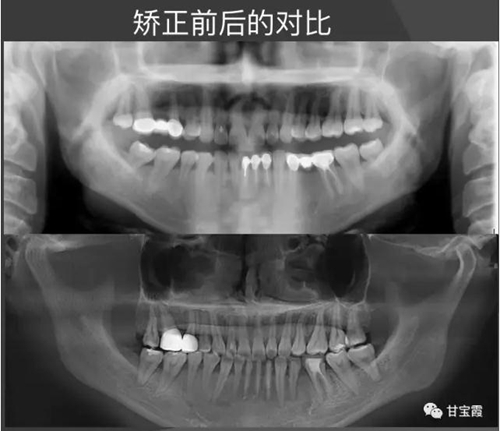

經(jīng)過(guò)28個(gè)月的矯正,大家可以看到原來(lái)的兩個(gè)缺牙間隙沒(méi)有了,舊的烤瓷牙換成了全瓷冠修復(fù)。下面的圖片是矯正前后的X線(xiàn)對(duì)比,

下圖是矯正前后的開(kāi)口頜像的對(duì)比,患者朋友看到這么好的治療效果,很后悔幾年前做的烤瓷修復(fù),還白白的磨了好牙。